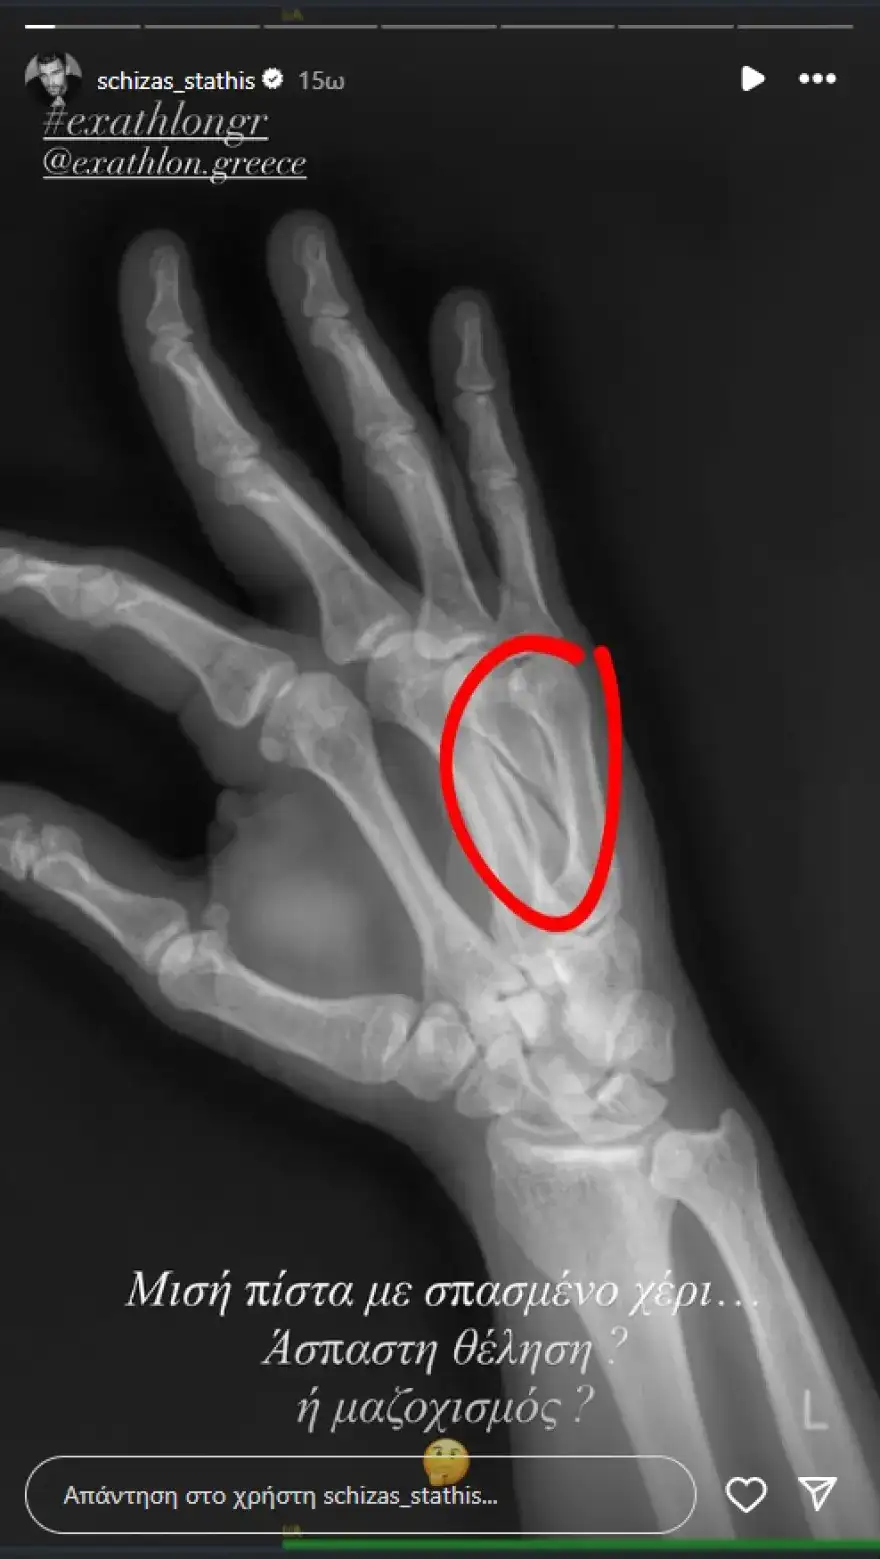

Η στιγμή του τραυματισμού του καταγράφηκε στο επεισόδιο του Σαββάτου (06/09), όταν στη διάρκεια της κούρσας σταμάτησε ξαφνικά, αντιλαμβανόμενος ότι είχε χτυπήσει σοβαρά. Οι γιατροί της παραγωγής έσπευσαν να τον περιθάλψουν, ενώ στη συνέχεια μεταφέρθηκε σε νοσοκομείο για εξετάσεις. Η ακτινογραφία έδειξε κάταγμα, γεγονός που σήμανε το τέλος της παρουσίας του στο ριάλιτι.

Λίγο αργότερα, ο ίδιος έκανε την πρώτη του ανάρτηση στο Instagram, δημοσιεύοντας την ακτινογραφία του τραυματισμένου χεριού. «Μισή πίστα με σπασμένο χέρι. Άσπαστη θέληση ή μαζοχισμός;» έγραψε.